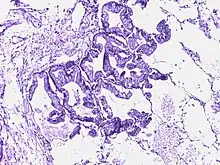

![]() | Papillary carcinoma thyroid | The phenomenon of orphan Anne eyes in papillary thyroid cancer. | Category: Histopathology of thyroid papillary carcinoma | papillary carcinoma |